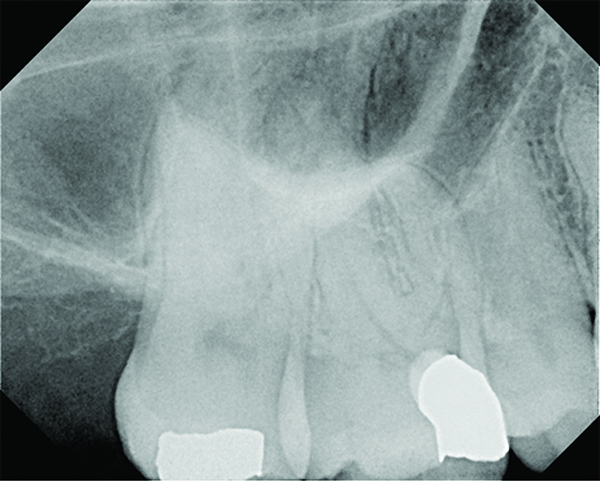

(4. AND 5.) This maxillary first molar was to have endodontic therapy following diagnosis of irreversible pulpitis.

Figure 4